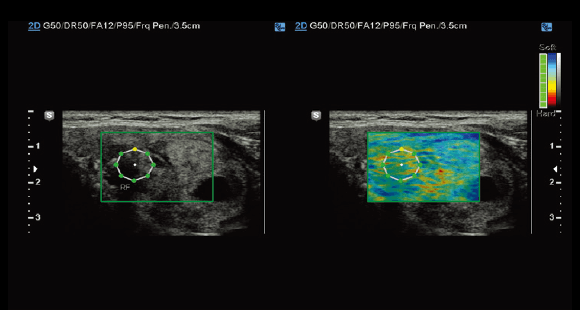

S-Shearwave

S-Shearwave detects the velocity of the shearwave propagated through the targeted lesion and displays the numerical measurement of stiffness In kPa or m/s together with a Reliable measurement Index (RMI)*. S-Shearwave has the potential to reduce the number of conventional liver biopsies by providing quantitative tissue characteristic information.

E-Breast™

Unlike conventional ultrasound elastography, E-Breast™requires to select only one ROI to calculate the strain ratio.

E-Thyroid™

E-Thyroid™ uses pulsations from the adjacent Carotid Artery and provides an assessment of thyroid lesions.